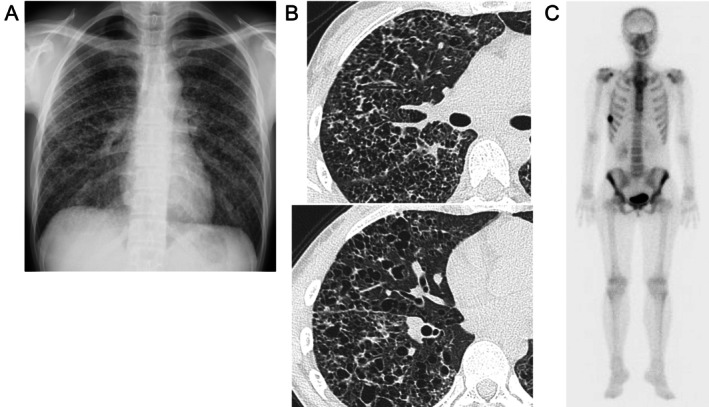

Pulmonary Langerhans cell histiocytosis (PLCH) is a rare diffuse lung disease that is strongly associated with cigarette smoking, with the BRAF V600E mutation identified in approximately half of all cases. In Japan, combination therapy with BRAF and MEK inhibitors has recently been approved as an alternative treatment option. We report the case of a 30-year-old woman diagnosed with BRAF V600E-mutant PLCH who was treated with dabrafenib in combination with trametinib. Chest computed tomography performed 3 months after the initiation of therapy demonstrated improvement in pericystic opacities, and this radiological response was sustained for over 1 year. Improvements in exercise tolerance, pulmonary function, and pulmonary haemodynamics have been observed clinically. These findings suggest that dabrafenib plus trametinib is a promising therapeutic option for patients with PLCH.